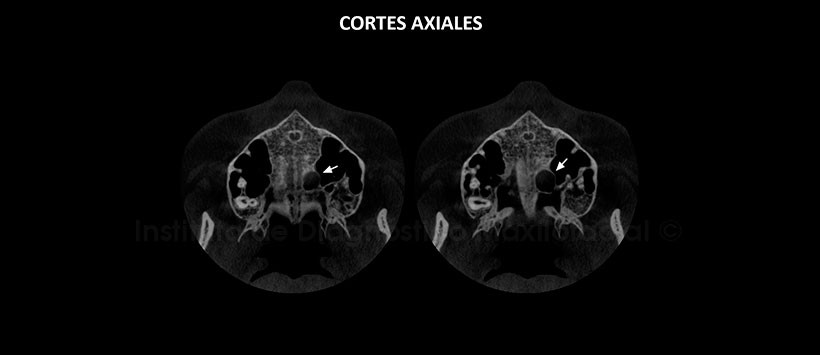

A la evaluación de la tomografía volumétrica (CBCT) mediante cortes axiales (Figura 2), coronales (Figura 3), sagitales (Figura 4), se evidencia una lesión hipodensa de límites definidos, bordes corticalizados, localizado en el lado izquierdo del tercio medio del paladar duro. La lesión ocasiona desplazamiento y adelgazamiento del piso de fosa nasal, así como del contorno medio basal del seno maxilar, se aprecia además un aumento del tejido blando adyacente